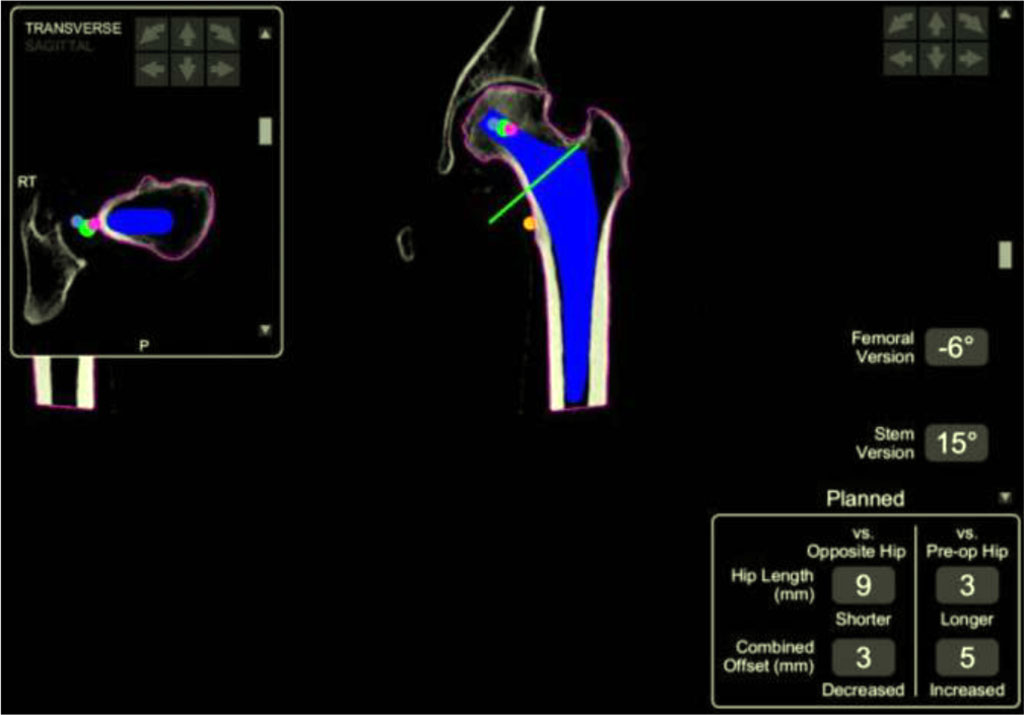

Another useful tool is preoperative three- dimensional modeling, which enables the development of a surgical strategy, reduces operation time, and helps prevent complications arising from individual anatomical variations. This approach significantly facilitates a personalized treatment plan for each patient [47]. Research results show that the use of robotics employing computed tomography (CT) and 3D reconstruction improves radiological outcomes by increasing the safe placement of the prosthesis compared to the manual technique. Studies do not indicate any significant difference in intraoperative or early postoperative complications compared to the manual technique. Despite promising short-term results, there is a lack of comprehensive studies with longer follow-up periods that could confirm the long-term impact of using surgical techniques supported by robotic tools [48].

Fig 6. Three-dimensional reconstruction of anatomical structures [49].

Fig 7. Screen displaying preoperative confirmation of the femoral stem size, offset, and version prior to cutting the femoral neck. [49].